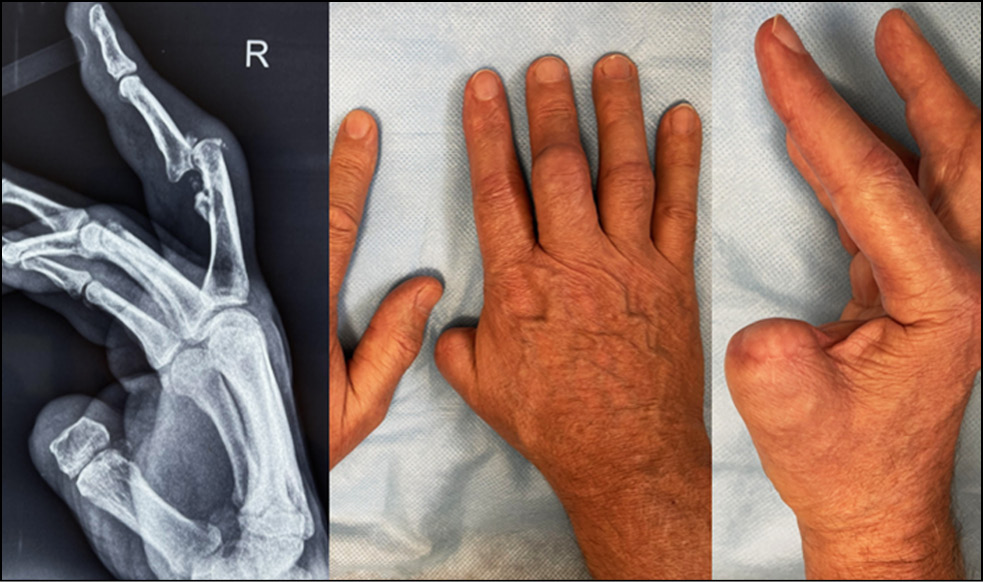

Fig. 1. The appearance of the limb.

Fig. 2. X-ray picture.

Fig. 14. Appearance and X-ray picture.

Fig. 15. Marking of computed tomography.